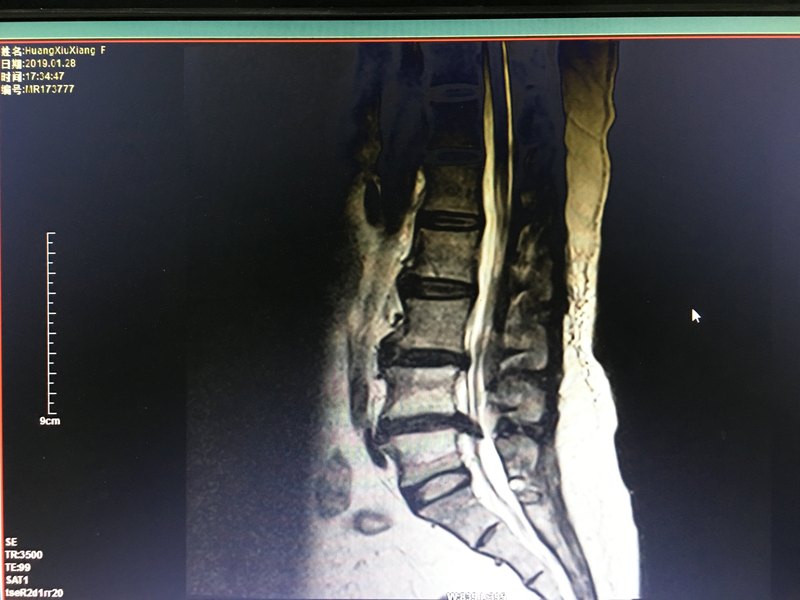

- 精選 椎間孔鏡微創(chuàng)手術(shù)治療腰椎間盤突出癥

采取椎間孔入路 取出的腰椎間盤髓核組織 充分松解受壓神經(jīng)根 術(shù)后直腿抬高實驗陰性,患者的下肢疼痛即刻緩解、消失,再沒有出現(xiàn)小便不能自控的情況。目前經(jīng)皮椎間孔鏡微創(chuàng)手術(shù)是治療腰椎間盤突出癥的主流、高效方法,該技術(shù)采取局部麻醉,手術(shù)切口8mm,術(shù)后6小時起床,1月后參加工作,損傷小,療效高,不易復(fù)發(fā)。宜春市人民疼痛科已經(jīng)安全有效開展200余例,歡迎病友前來咨詢、就診。